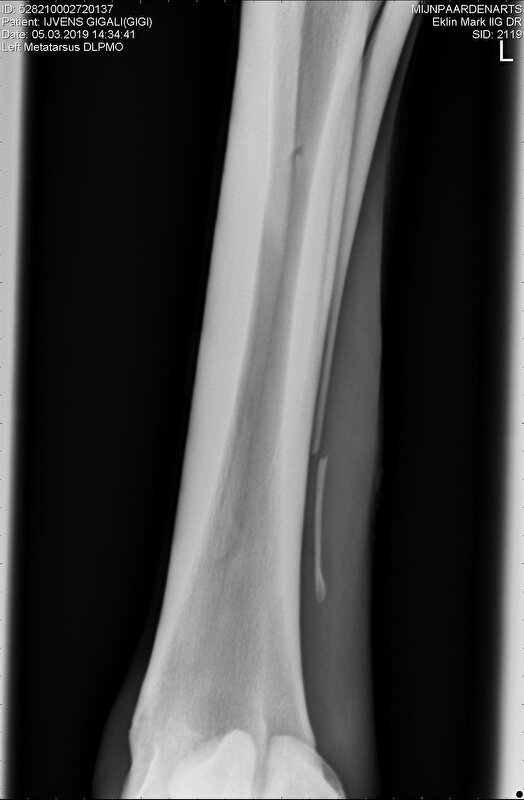

Hierbij de foto's degene die ik naast elkaar gezet heb is links van 5 maart en rechts van 29 maart.

Links dus 5 mrt en rechts 29 mrt